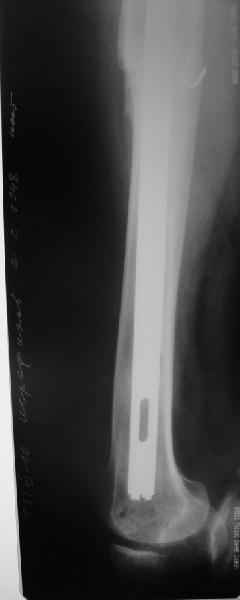

О качестве сращения перелома тоже сказать трудно. Выраженной мозоли нет. В боковой проекции отломки накладываются друг на друга. В прямой проекции зона перелома в наружной части закрылась не полностью. Возможно причина тому - недогрузка кости.

Сейчас опорную нагрузку на бедро берет на себя система от бедренного компонента эндопротеза до проксимального винта в интрамедуллярном гвозде. Свидетельство тому - реакция кортикала утолщением вокруг того самого винта. Таким образом вся кость от верхушки б.вертела до проксимального винта не испытывает физиологической осевой нагрузки. Результатом этого могут стать следующие последствия друг друга не исключающие: 1) все будет хорошо до перелома опорной системы по винту(ам) или в месте соединения штифта с ножкой или еще где-либо, 2) исключенная из-под нагрузки кость будет терять в количестве и качестве, что не очень (или очень не) хорошо для возможных будущих ревизий (тьфу-тьфу!!!).

Винты точно были под нагрузкой до сращения, и утолшение кости вокруг них образовалось тогда, и не может рассосаться мгновенно, даже если винты удалить. То есть это не обязательно свидетельство того, что и сейчас нагрузка идет в основном на дистальные винты.